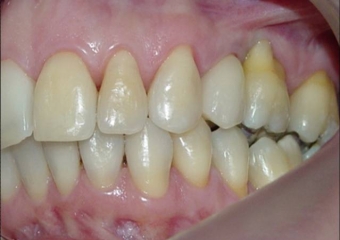

Imagens iniciais, observando a ausência do pré molar superior